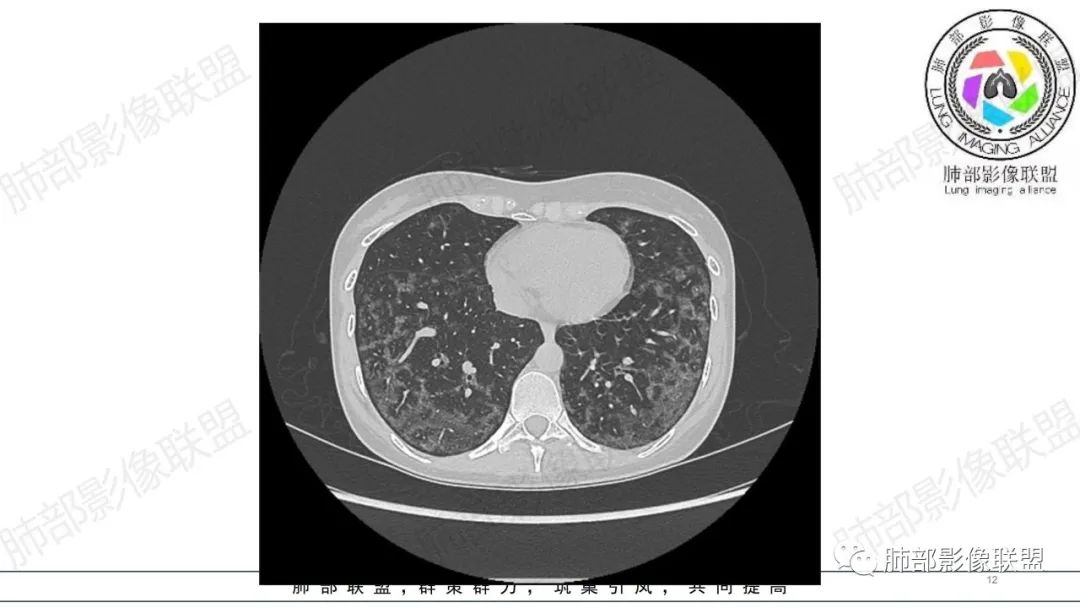

影像资料

34岁女性患者,“哮喘”病史30年,近期有可疑刺激性气体吸入史;因乏力半年,咳嗽、憋气、发热4天就诊;6.1CT提示双肺广泛毛玻璃影及粟粒样结节,胸膜下闲置及血管周闲置,可见树丫征,部分小叶间隔增厚。考虑:1.过敏性肺泡炎,有可疑刺激气体接触史,胸膜下闲置,广泛毛玻璃影,地图样分布,粟粒结节边界模糊,支持过敏性肺泡炎,但糖皮激素治疗效果不佳,且动态复查血常规血红蛋白进行性降低,过敏性肺泡炎 不符合;2.肺含铁血黄素沉积症:患者30“哮喘”病史,可能为肺含铁症状,肺部CT提示双肺弥漫毛玻璃影及粟粒结节影,中下肺明显,肺底部分小叶间隔增厚,近期咳嗽、憋气、发热,血常规血红蛋白进行性下降,考虑肺含铁急性期症状,但临床无咯血症状,肺含铁不典型。综合考虑:肺含铁血黄素沉积症>过敏性肺泡炎。

年轻女性 ,急性喘息发热,肺部影像弥漫磨玻璃密度,部分细小腺泡结节,胸膜下黑线显示,短期复查,病变密度增高,下肺明显,血管周围肺组织累及较少、且逐渐成小叶间隔分布。考虑弥漫肺泡内病变,并经淋巴道转移,下肺比上肺明显,多为免疫细胞功能下肺较强。1.过敏性肺泡炎,有相关病史,三层密度特点、头尾测分布,符合。2 肺泡微石症,多有钙化,且缓慢起病,病程不太符合,放待排。3 吸入相关肺损伤,有病史,疾病演变过程也符合渗出-肉芽肿改变,建议详细询问病史。4 感染性病变,结核?病变气道分布为主,如此弥漫且没有树丫不符合。5.巨细胞病毒,可以磨玻璃 结节 改变,没有免疫缺陷病史。最后考虑吸入所致 1过敏性肺泡炎、吸入性肺损伤 鉴别肺泡微石症。

肺内气腔磨玻璃结节,肝脾肿大,治疗后间质改变,弥漫大B可能